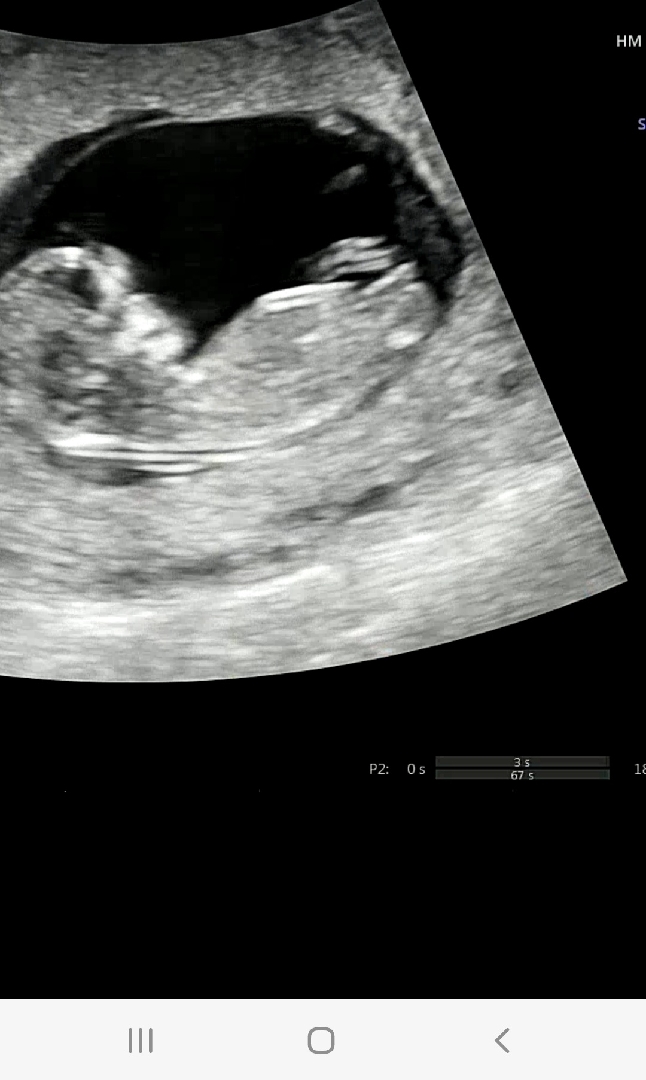

딸일까요?아들일까요?

아셋맘입니다. 성별 궁금해서요 ㅠ

딸같아요!!!